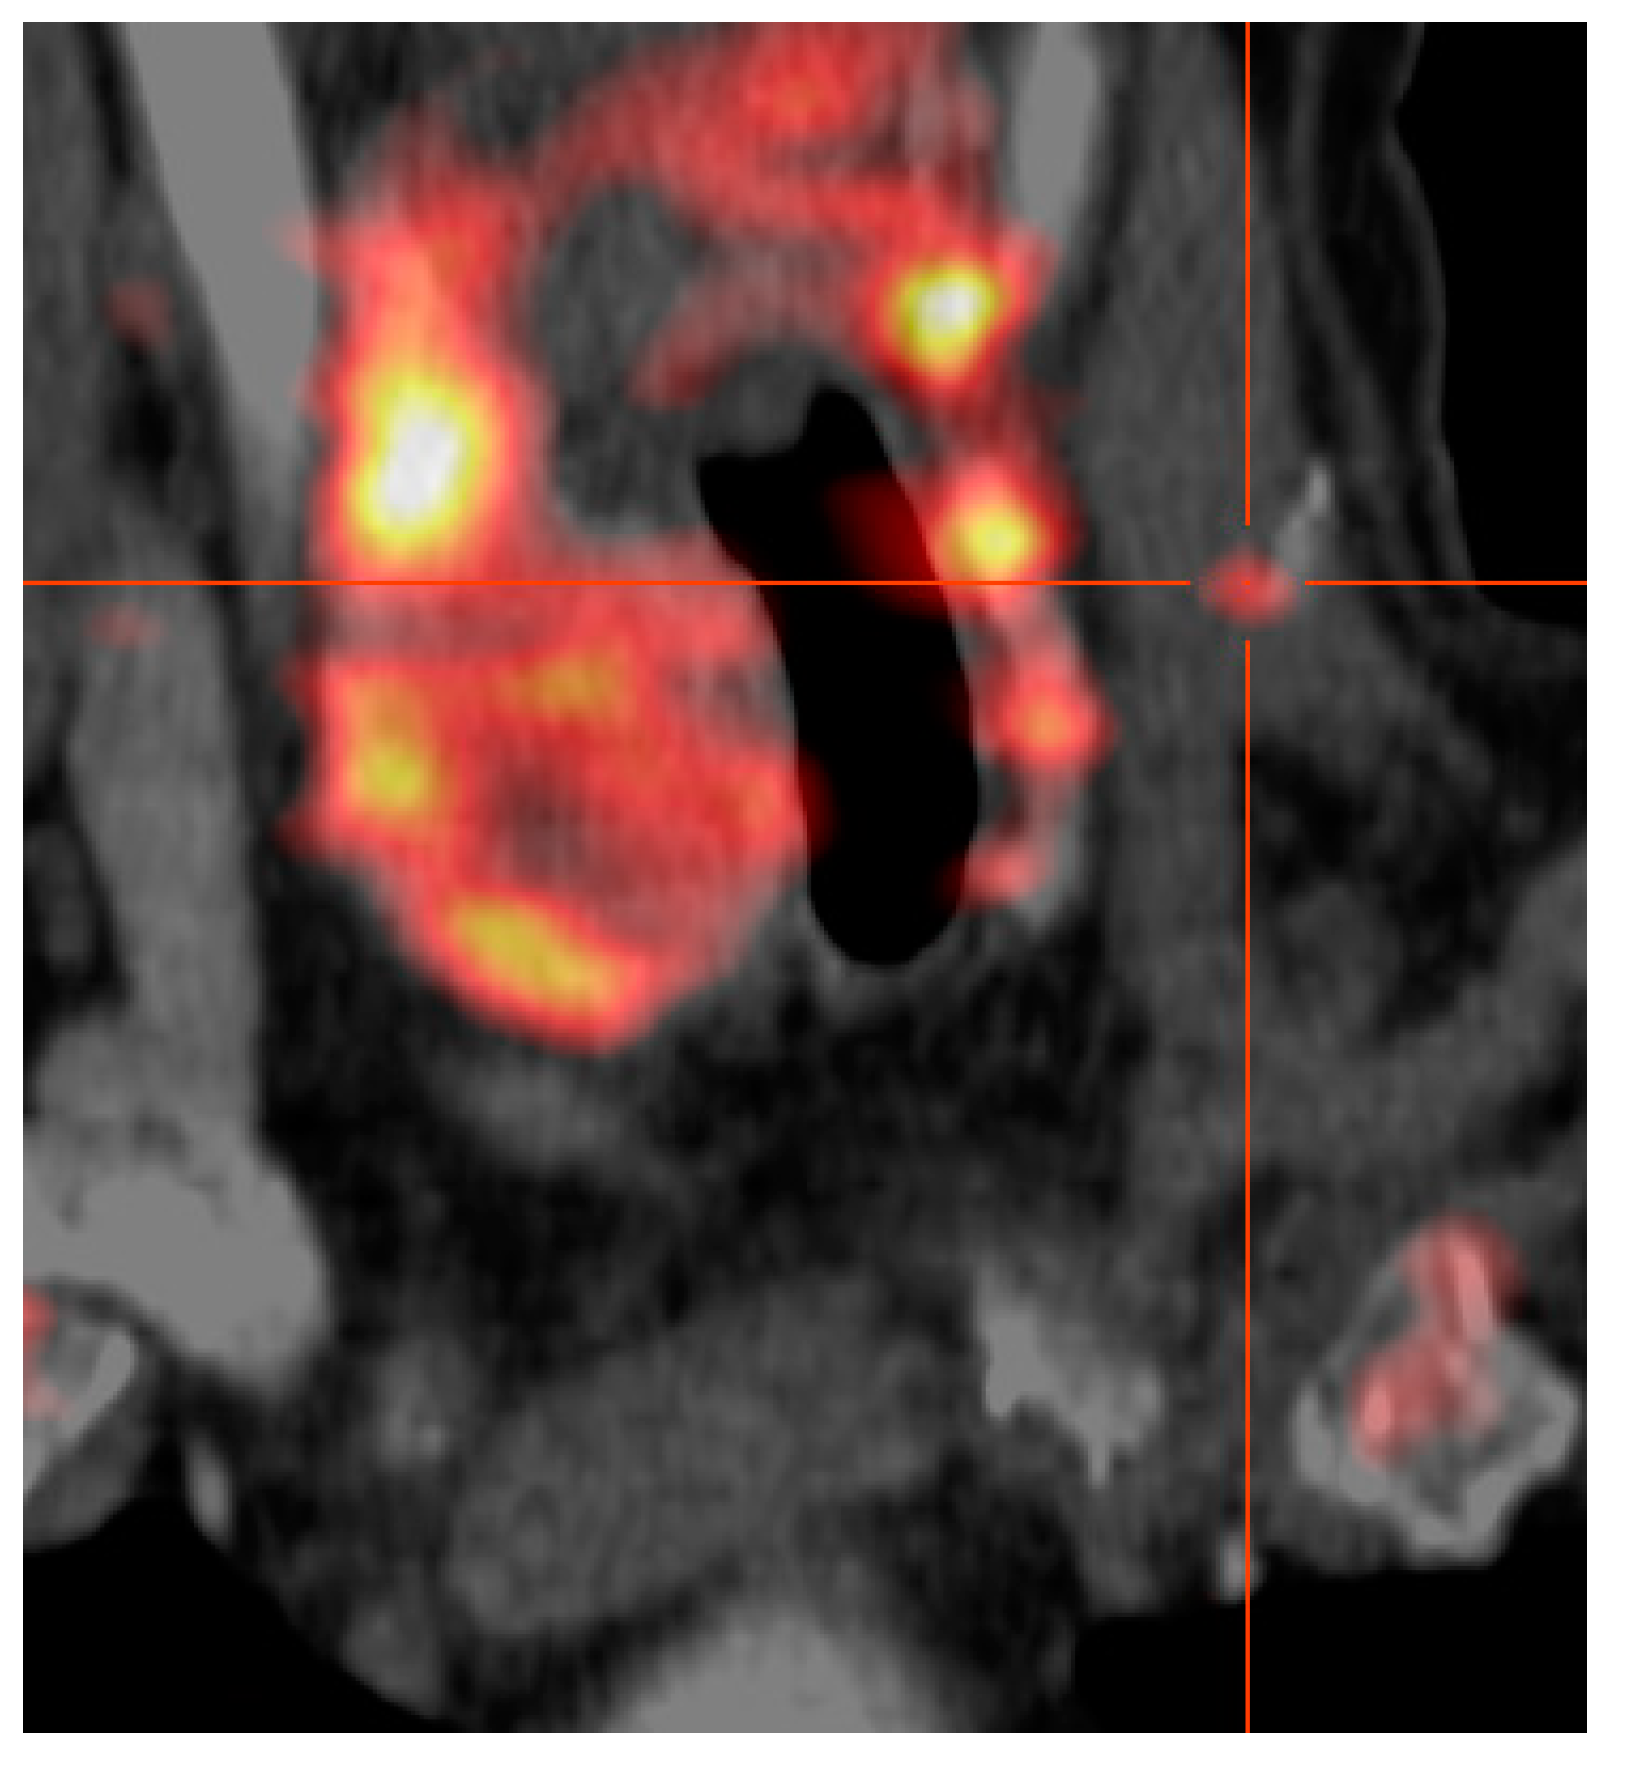

[18F]fluoro-ethylcholine-PET Plus 4D-CT (FEC-PET-CT): A Break-Through Tool to Localize the “Negative” Parathyroid Adenoma. One Year Follow Up Results Involving 170 Patients

2. Materials and Methods

3.2. Localization of PA by Ultrasound, MIBI-Scintigraphy and FEC-PET-CT plus 4D-CT